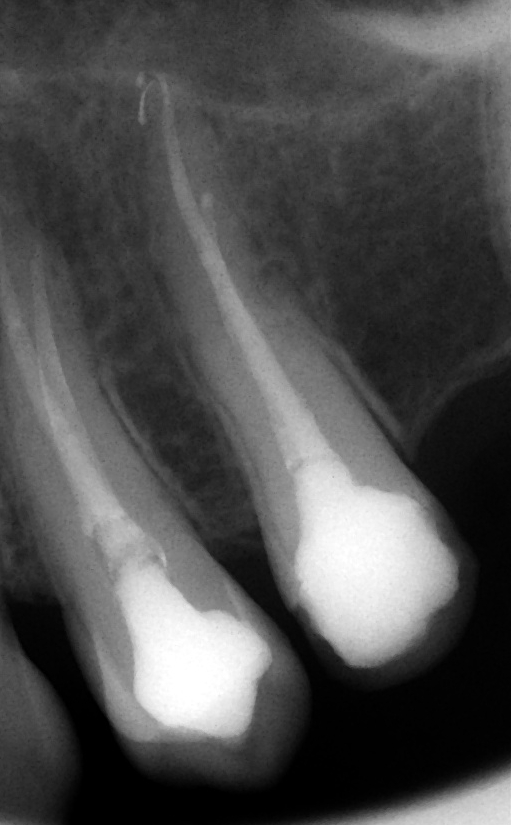

Zaplněné a uzavřené kořenové kanálky

Kontrolní rentgen po zaplnění